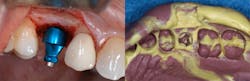

Importance of radiographs

Component mating is critical with implant prosthetics. As the connection is subgingival, it is difficult to visualize how well the prosthetic will connect to the implant connector. Bone or soft tissue may hamper full seating, or the abutment may be rotated slightly so that it and the implant connector do not ideally align. Tightening the fixation screw may provide the perception that the parts are mated, when radiographically they are not. It is also important to radiographicallyConclusion